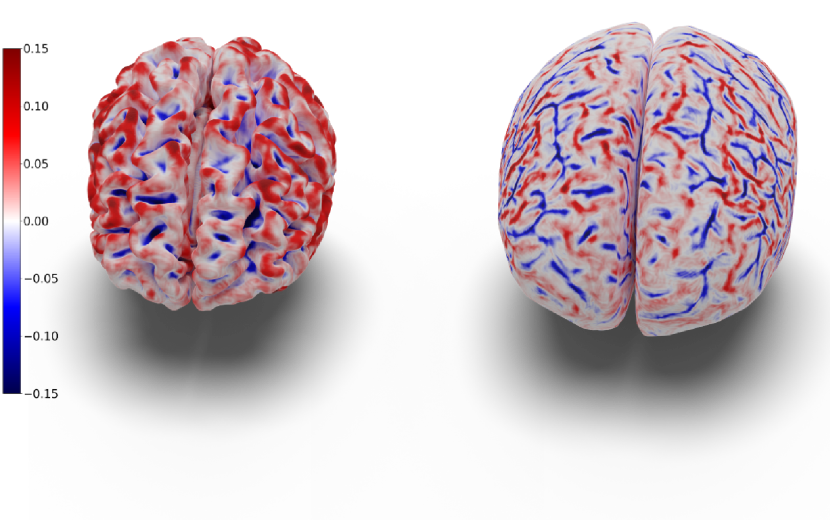

In our experiments, we noticed that CorticalFlow produces more geometrically accurate surfaces than the other methods. On average, it presents better geometric metrics across all the cortical surfaces. In addition, as shown in Figure 3, CorticalFlow errors are smaller () and evenly spread across the surface compared to the other methods. In contrast, NMF and DeepCSR can present substantial errors (). The former has its error spread across the entire surface, while the latter can produce large errors at specific regions.

CorticalFlow is also more robust than the competitors presenting lower error variation across individuals as suggested by the smaller standard deviation of the geometric metrics computed. Interestingly, CorticalFlow is also more robust to MRI artifacts even when the pseudo-ground-truth surface has poor quality. For instance, in Figure 4, CorticalFlow predictions are still plausible for a blurry input MRI while FreeSurfer fails significantly to generate appropriate surfaces for the same input. These examples support our claim that a regular parametrization allows us to reduce non-plausible and non-diffeomorphic predictions that our model cannot learn by construction.